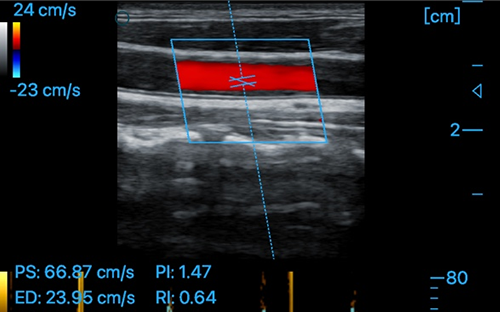

Carotid + CF + PW + Auto Trace

Carotid + CF + PW + Auto Trace

Radial Artery + CF

Measure Function:OB,distance,area of a circle,Velocity,blood flow measure,fetal heart,heart rate